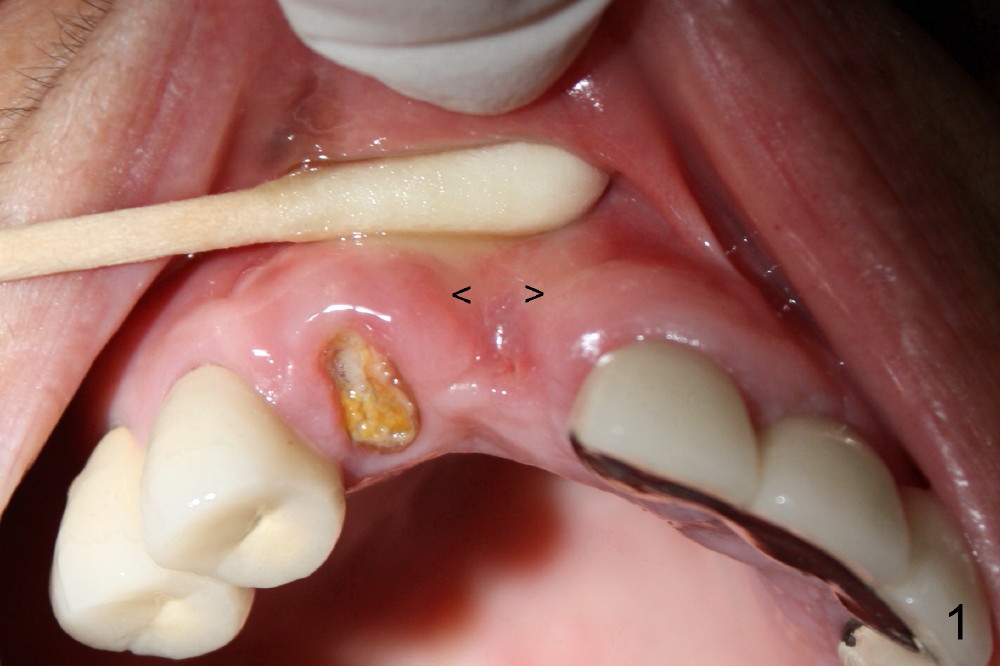

Finally the displaced implant is exfoliated itself, leaving a crater (Fig.1 arrowheads). CBCT shows the knife-edged ridge post exfoliation of the implant at the site of #7 (Fig.5, as compared to that prior to exfoliation). After using 1.5 mm pilot drill at 17 mm and 2.0 mm at 14 mm (Fig.5 insert), a 3.0x17 mm one piece angled (15 º) implant is placed (Fig.2, 10). Palatal view reveals that the implant is placed buccally (Fig.3); ideally the implant should be more palatal (Fig.3 insert: circle). Please take postop CBCT to confirm the placement. The buccal placement is partially related to the elongated tooth (Fig.4).